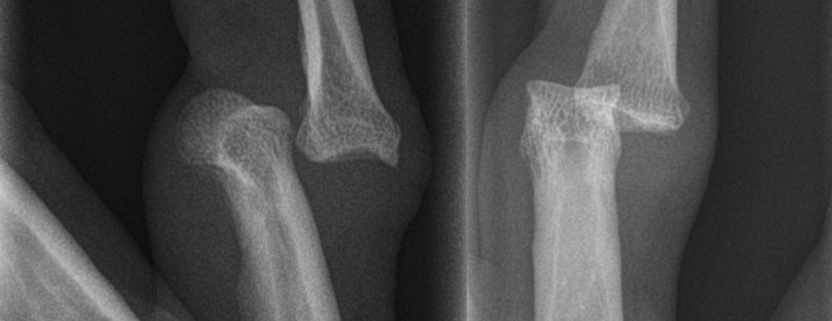

Diagnosis of PIP joint injuries usually involves a physical examination of the hand where your doctor will assess the area’s mobility, sensitivity, and appearance. Imaging tests like X-rays or, in more complex cases, MRI scans, are performed to get an in-depth understanding of the injury degree and type.